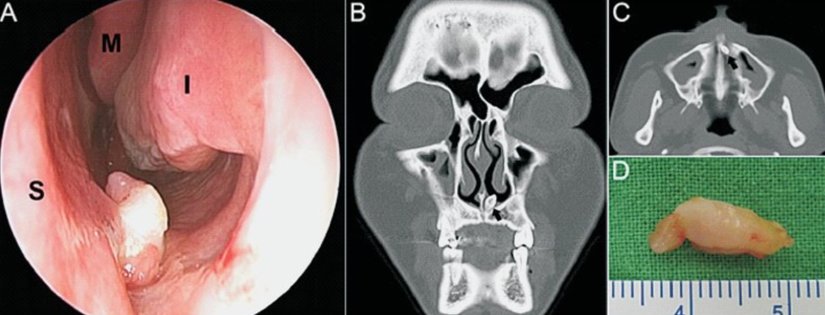

Sırası ile Endoskopik (A), Tomografi (B,C) ve postoperatif görüntülerini gördüğümüz bu ektopik diş vakası ise hastaya burun tıkanıklığı, yüze yayılan ağrı ve yüzde baskı hissi şikayetleri vermiştir. Dişin çıkarılmasını ve rinoplastiyi içeren bir operasyondan sonra hasta sağlığına kavuşmuştur.